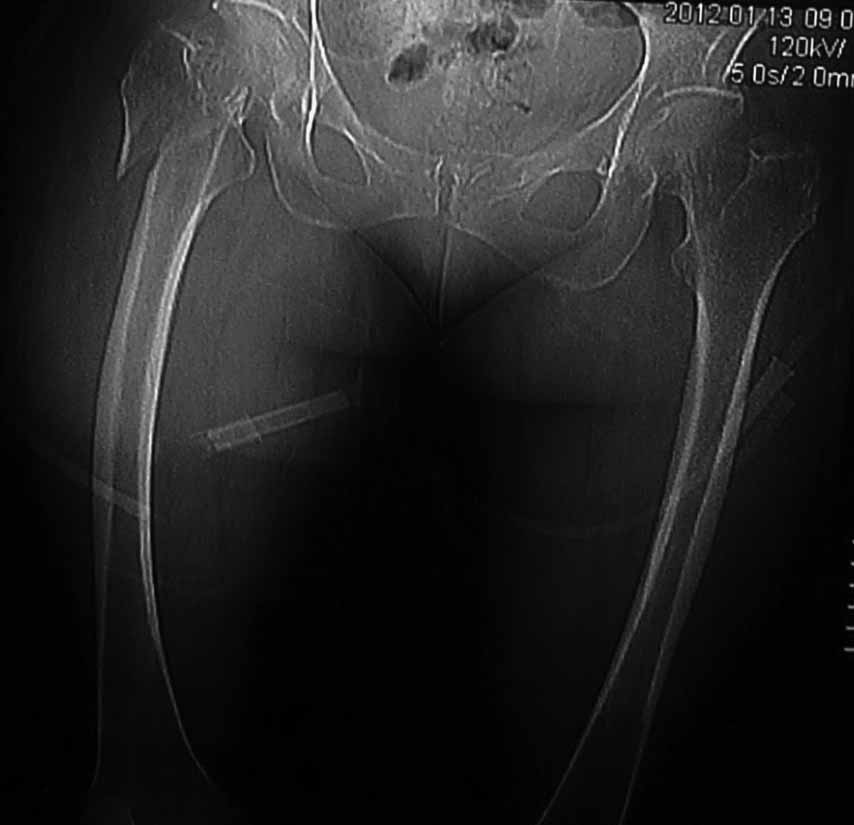

Пациентка 53 лет. ДТП 09.01.12: сочетанная травма: перелом 2-5 ребер справа, ушиб легких; перелом обеих лонных костей без смещения; закрытый перелом проксимального конца правой бедренной кости; открытый оскольчатый внутрисуставной перелом проксимальных концов костей правой голени.

В нашей клинике 11.01 выполнен минимально инвазивный остеосинтез большеберцовой кости (снимки до операции не перефотографировал) с пластикой перемещенными лоскутами дефекта, образовавшегося вследствие некроза кожи на передней поверхности голени. Бедро одномоментно делать не стал, не было уверенности в наличии перелома на уровне шейки. Во время операции смотрел тазобедренный сустав под ЭОПом, головка неподвижна. После операции повторили КТ, стало очевидно, что имеется субкапитальный перелом.

И еще: не явится ли препятствием для введения гвоздя дугообразный изгиб диафиза бедренной кости? Вершина деформации расположена на 110мм дистальнее проксимального края малого вертела. Это я по КТ измерил точно. Можно, конечно, думать о короткой ножке. Но обеспечит ли она достаточную фиксацию при таком переломе?